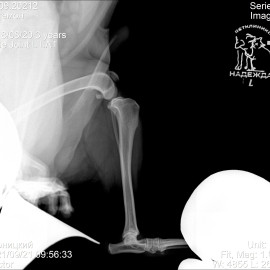

Наш пациент собака по кличке Артемон. Обратились с жалобами на остро развившуюся хромоту на заднюю левую лапу. После осмотра и рентгенологического исследования был поставлен диагноз - разрыв передней крестообразной связки левого коленного сустава. Была проведена операция- TPLO.

Снимки 1-2 до проведения операции.